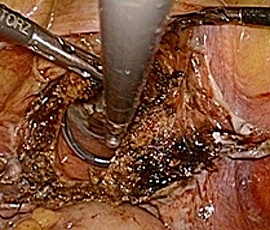

腹腔鏡下(補助下)膵体尾部切除術の実際

従来の開腹手術では15cm以上の皮膚切開が必要で、美容面(整容性)や術後の痛みなど

が問題でした。一方、腹腔鏡手術では、4cmの小切開と5〜10mmの3〜4ヶ所の傷で

手術が可能です(図)。専用の器械を用いて膵切離を行い、小切開創から体外に取り出

します。術後の傷は小さく美容面で優れており、また術後の痛みも軽減されます。また

症例によっては完全腹腔鏡下膵体尾部切除を行う場合もあります。